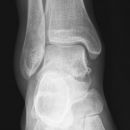

Totale Talusluxation